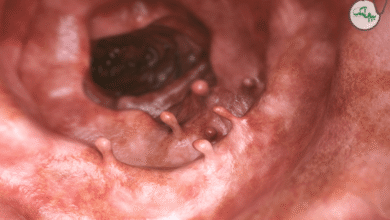

انسداد مجاری صفراوی

بسته شدن مجاری صفراوی، یعنی انسداد مجرای که صفرا را از کبد از خارج می کند ممکن است باعث بروز این بیماری شود. این انسداد ممکن است به علت بیماری هایی مثل سرطان لوزالمعده یا سنگ کیسه صفرا اتفاق بیفتد. اگر مجاری صفراوی مسدود شود، صفرا در کد باقی مانده و بیلی روبین دوباره به خون بر می گردد. این نوع یرقان ممکن است همراه با علائمی مثل خارش، پر رنگ شدن ادرار و کم رنگ شدن مدفوع دیده شود.